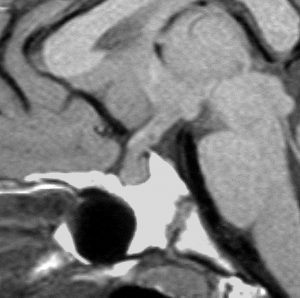

血清HCGが2.1mIU/ml,尿崩症で発症した思春期男児です。石灰化はありませんし,脂肪組織なども混在しません。生検術をしなくてもgerminomaと診断できます。でも簡単なので,経鼻的な生検術を行った方がいいです。

この例は18歳,HCG 0.1mIU/ml,尿崩症で発症しました。神経下垂体ジャーミノーマなので,下垂体前葉のみが残って後葉から視床下部が腫瘍化しています。よくよく見ると松果体にもごく小さな腫瘍があります。右のCISS画像で松果体の腫瘍化が明瞭です。

経鼻生検術で下垂体後葉部分がgerminomaということを確認してからICE (IFO/CDDP/VP-16)を1コース加えて3週間後の画像です。腫瘍は灰白隆起の部分を残してほぼ消失しています。松果体部の腫瘍も消えています。典型的なgerminomaの化学療法反応性を示しています。下垂体前葉機能は正常,尿崩症も少し良くなりました。